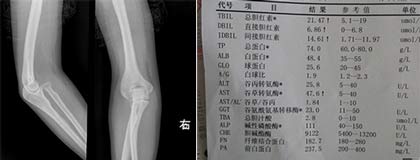

(图:刘先生入院后所做的CT检查及化验单)

体格检查:T38℃,R21次/分,P78次/分,BP110/80KPa,巩膜无黄染,浅表淋巴结不肿,无颈静脉充盈,双肺呼吸音清,心律齐,肘关节疼痛明显,下膝关节疼痛剧烈。

化验单:血沉21mm/h,类风湿因子59IU/ml,抗链球菌溶血素267/ml,超敏C反应蛋白18mg/L。